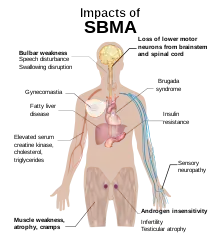

Neuromuscular symptoms include muscle weakness and wasting of the limb, bulbar and respiratory muscles, tremor, fasciculations, muscle cramps, speech and swallowing difficulties, decreased or absent deep tendon reflexes, and sensory neuropathy. Other manifestations of SBMA include androgen insensitivity (gynecomastia, erectile dysfunction, reduced fertility, testicular atrophy), and metabolic impacts (glucose resistance, hyperlipidemia, fatty liver disease).[3][5][10]

Metabolic disturbances have also been reported in SBMA patients, with increased risk of insulin resistance, fatty liver disease, hyperlipidemia, and electrocardiogram (ECG) abnormalities. Impaired glucose homeostasis is a common feature of SBMA, and recent study found a significant correlation between insulin resistance and motor dysfunction in SBMA.[11][16] In a group of 22 patients with SBMA, evidence of fatty liver disease was detected in all individuals by magnetic resonance spectroscopy. In a second group, liver dome magnetic resonance spectroscopy measurements were increased in participants with SBMA relative to age- and sex-matched controls.[3][17] SBMA patients may have higher frequency of Brugada syndrome and other electrocardiogram (ECG) abnormalities, which if not detected, can lead to sudden death. There are no reports of cardiomyopathy. However, there are indications that SBMA patients may be more likely to have high blood pressure and elevated total cholesterol and triglycerides.[11][3]